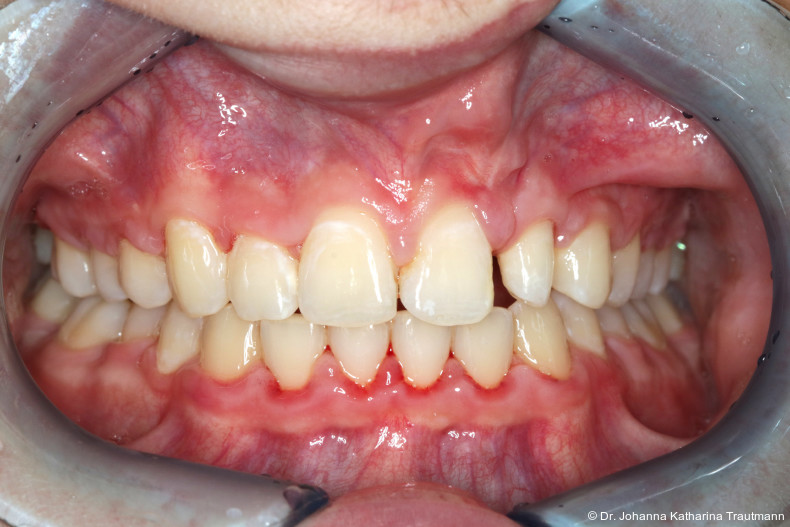

Auch im Rahmen der Zertifizierung durch das German Board of Orthodontics and Orofacial Orthopedics (GBO) wird dieser Aspekt gezielt hervorgehoben: Bewerberinnen und Bewerber sind aufgefordert, Fälle vorzustellen, die eine enge Kooperation verschiedener Fachdisziplinen dokumentieren und somit die Vielschichtigkeit und Tiefe der kieferorthopädischen Behandlungsmethoden aufzeigen. Hierdurch wird deutlich, dass die Kieferorthopädie sich nicht allein auf fachspezifische zahnmedizinische Themen fokussiert, sondern einen wesentlichen Beitrag zur allgemeinen interdisziplinären medizinischen Versorgung leistet. Der nachfolgende Fallbericht zu einem Patienten mit ein seitiger Lippen-Kiefer-GaumenSpalte zeigt exemplarisch, wie bei einem um fangreichen Behandlungs fall die Kieferorthopädie als zentrales Bindeglied zwischen den Disziplinen fungiert und damit maßgeblich zur funktionel len und ästhetischen Rehabilitation des Patienten beigetragen hat. Erstvorstellung Der Patient stellte sich im Alter von 11,5 Jahren auf Anraten einer niedergelassenen Kollegin in der Poliklinik für Kieferorthopädie der Universitätsmedizin Göttingen vor. Hauptanliegen war die Beurteilung einer möglichen Durch bruchsproblematik sowie die Indikationsstellung einer sekundären Osteoplastik im Rahmen einer einseitigen Lippen-Kiefer-Gaumen-Spalte.

Allgemeinanamnestisch berichtete der Patient über eine eingeschränkte Nasenatmung und nächtliches Schnarchen. Ein bestehendes Asthma bronchiale wurde medikamentös durch ein corticoides Bedarfsspray kontrolliert. Der CMD Kurzcheck nach Ahlers und Jakstat1 zeigte keine Auffälligkeiten. Extraoral fiel ein konvexes Profil mit ausgeprägter Kinnprominenz sowie enface der linksseitige Narbenzug mit charakteristisch abgeflachtem Nasenflügel auf.

Das Fernröntgenseitenbild zeigte eine skelettale Klasse IIAnomalie mit einem Wits von 5,6 mm, bei einer tiefen Konfiguration (ML NL = 16,5°) mit bialveolär retrudierten Fronten (OK1NA = 5,9°; UK1NB = 10,4°), was sich auch in der Modellanalyse widerspiegelte. Hier zeigte sich zudem ein schmaler Oberkiefer mit multiplen Kippungen und Rotationen in der Front, einem hypoplastischem 22 sowie einer Mesialwanderung des 16. Des Weiteren zeigte sich eine asymmetrische Bisslage mit 1 PB distal rechts und ½ PB distal links bei einem Overjet von 2,5 mm sowie einem Overbite von 5 mm. Während im Unterkiefer bereits die zweite Zahnwechsel phase begonnen hatte, zeigte sich im Oberkiefer noch kein Wechsel in den Stützzonen. Gerade bei Patienten mit Spaltbildungen ist eine engmaschige Überwachung des Durchbruchs der oberen Eckzähne essenziell. Während bei der Allgemeinbevölkerung die Prävalenz von verlagerten Eckzähnen bei ca. 2,8 Prozent liegt2, ist diese bei Patienten mit Lippen-Kiefer-Gaumen-Spalten um den Faktor 10 erhöht.3, 4 Als klassische Risikofaktoren gelten zudem Platzmangel, transversale Enge aber auch Fehlstellungen, Nichtanlagen oder Hypoplasien der zweiten Schneidezähne. Diese übernehmen normalerweise die Funktion der Leitschiene für den S-förmigen Durchbruch der Eckzähne. Im vorliegenden Patientenfall kommen also mehrere Risikofaktoren für eine Verlagerung zusammen, was die rechtzeitige Diagnostik zur Abklärung einer Durchbruchsproblematik rechtfertigt. Da im Spaltbereich auch zusätzlich ein ausgeprägtes Knochendefizit vorliegen könnte, sollte auch immer die Option einer sekundären Osteoplastik abgewogen werden, deren Indikation und Timing optimal zum Durchbruch der Canini angepasst werden sollte.5